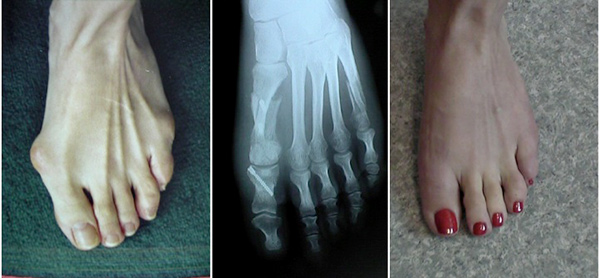

انحراف شست پا که به آن هالوکس والگوس نيز مي گويند، نوعی مشکل و برجستگي استخواني است که به طور معمول از کنار انگشت شست پا خارج مي شود.

انحراف شست پا  Bunions که به آن هالوکس والگوس نيز مي گويند، نوعی مشکل و برجستگي استخواني است که به طور معمول از کنار انگشت شست پا خارج مي شود.عوامل قابل کنترل و غیر قابل کنترلی وجود دارند که یک فرد را برای ابتلا به این مشکل مستعد تر می سازد. یک پزشک معمولاً با دیدن پای شما می تواند یک  انحراف شست پا را تشخیص دهد. اکثر اوقات این مشکل با روشهای مراقبت از خود درمان می شود ، اما ممکن است در برخی موارد نیاز به جراحی وجود داشته باشد.